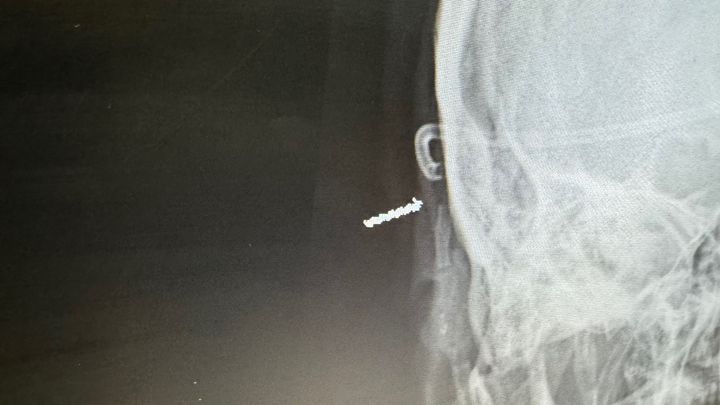

Hello my name is Michael Langley. I’m 35 years old and have lived in rock springs my whole life. I have 4 kids and a beautiful wife named Tiffany. Recently my family has fallen on pretty hard times due to medical problems with myself. Just some back history: I have had a arachnoid cyst in my brain my whole life that has required several brain surgeries. I have been good and stable for over 10 years until 2 months ago when seizures began. After meeting with neurology and neurosurgery we have found the shunt in my brain is broke which will require another brain surgery to fix. This is a long process and we have no time frame for surgery at this time. In the mean time we are having to make several trips to salt lake and they are trying to control seizures with meds.